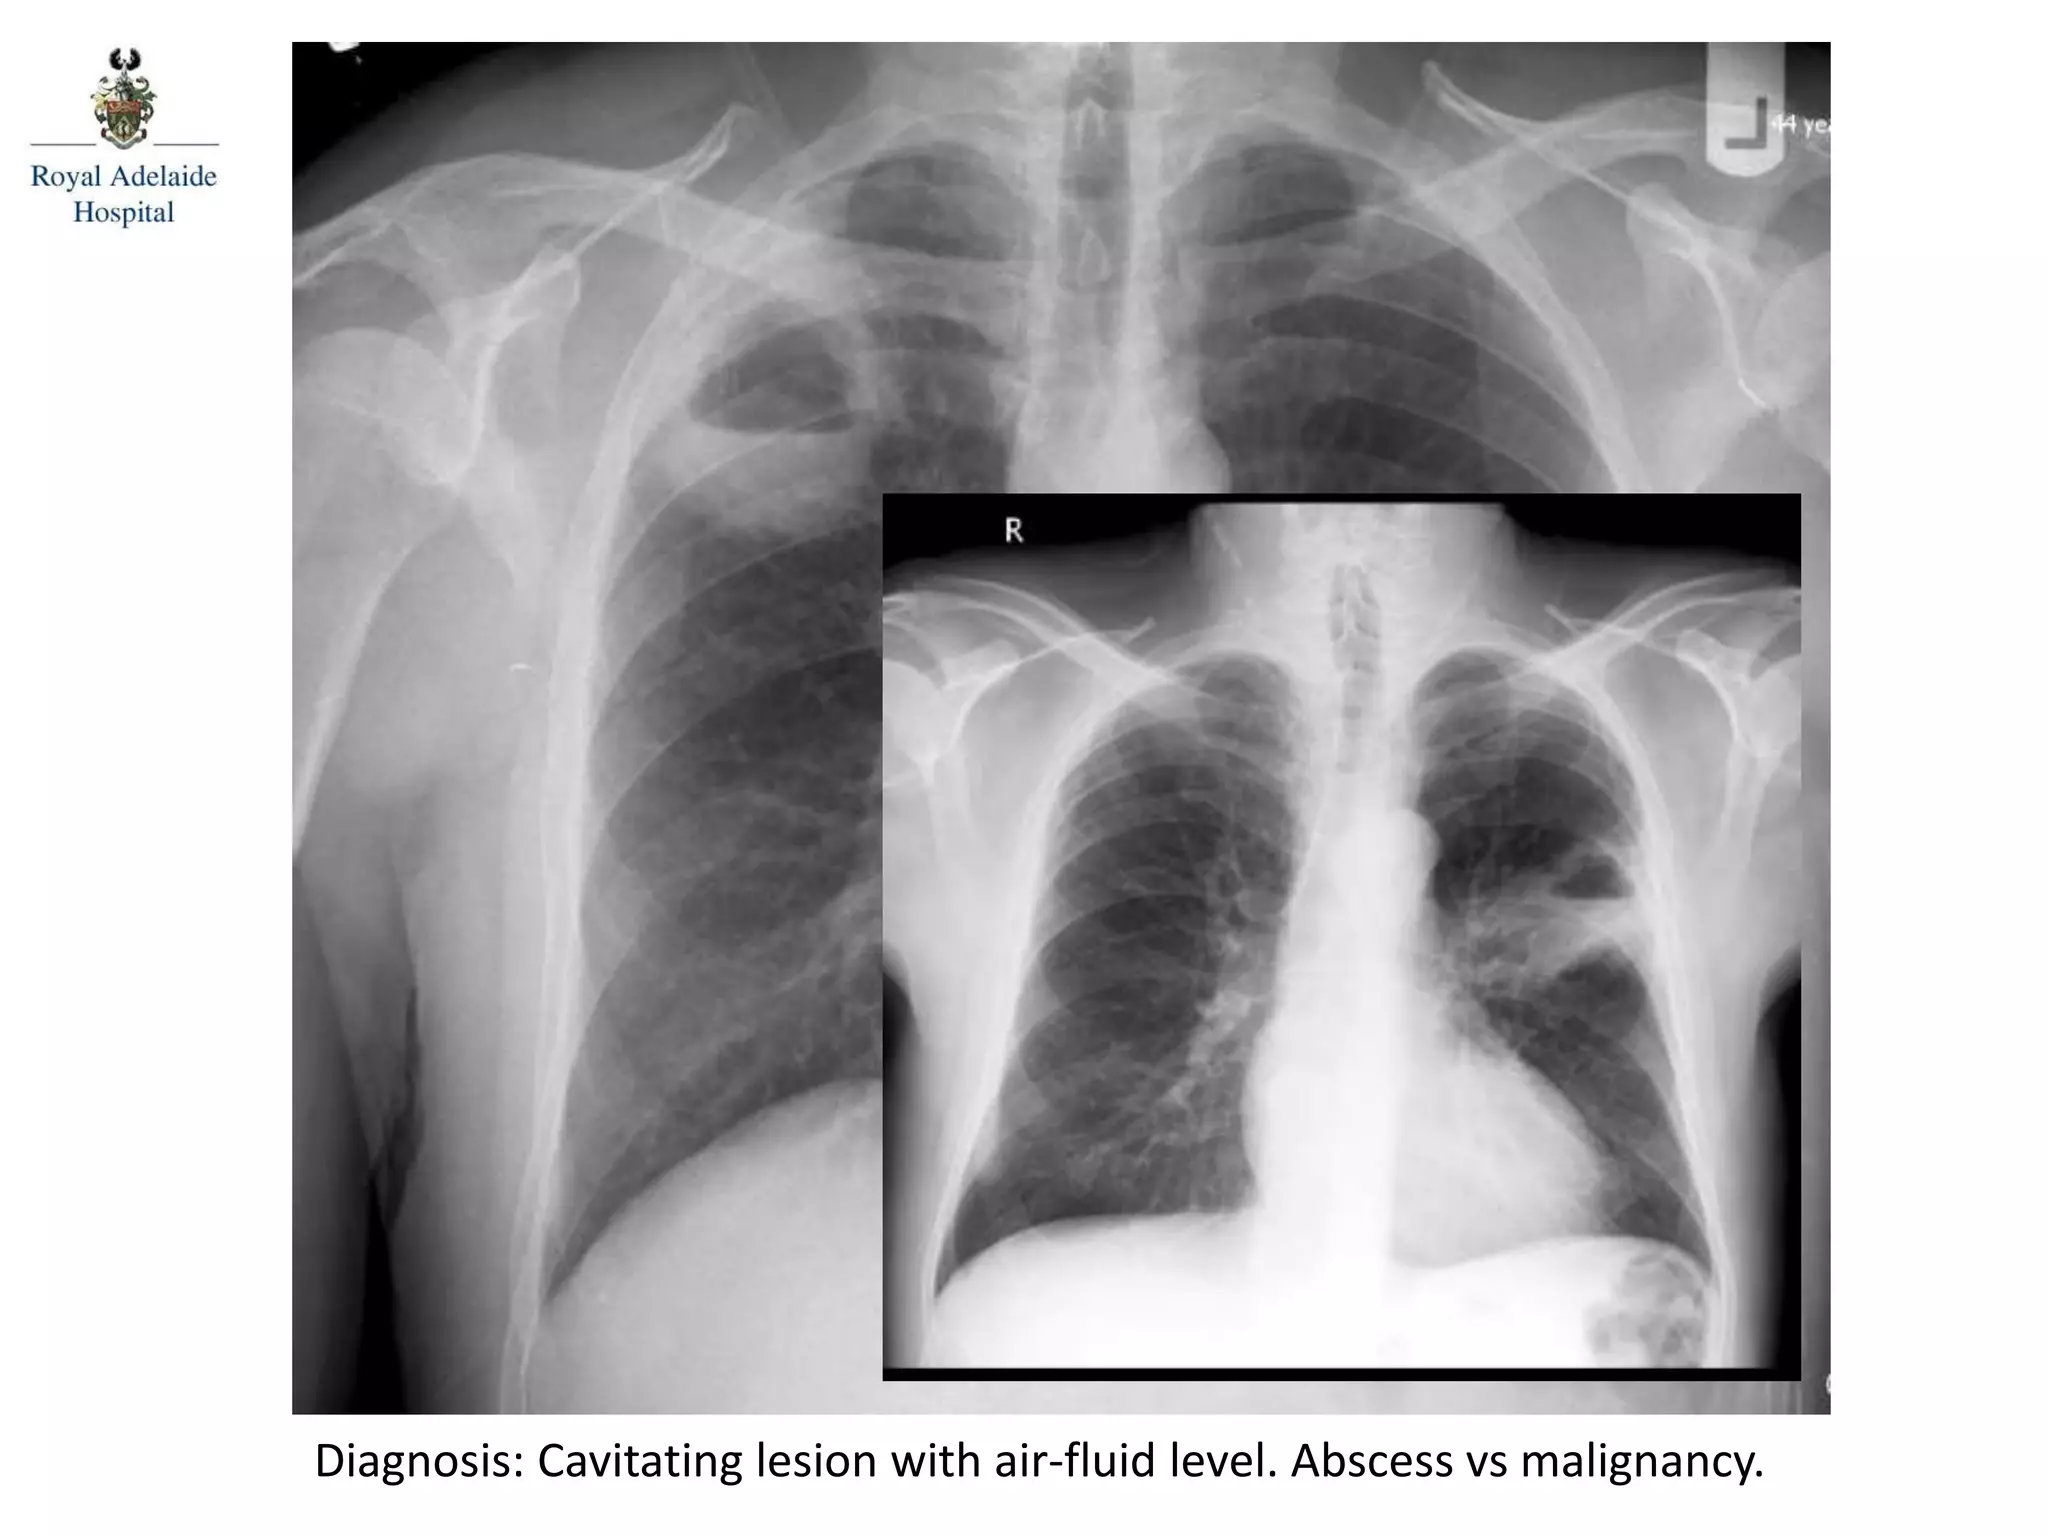

Diagnosis: Cavitating lesion with air-fluid level. Abscess vs malignancy.